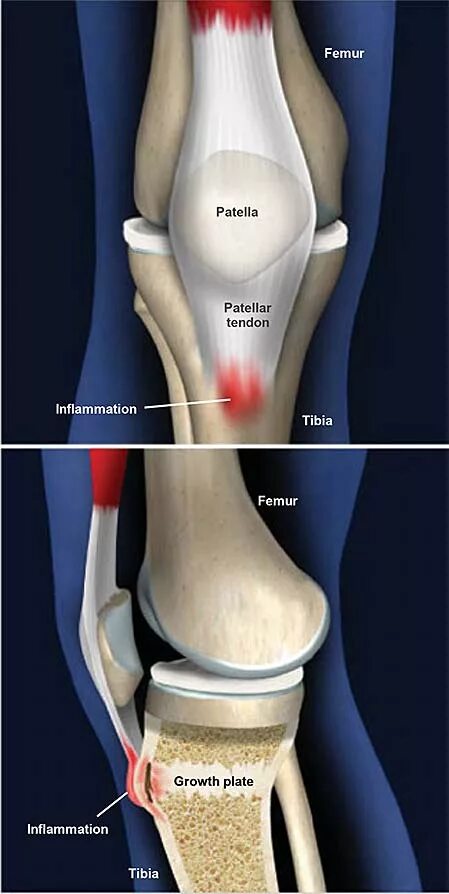

Синдром осгуда шляттера